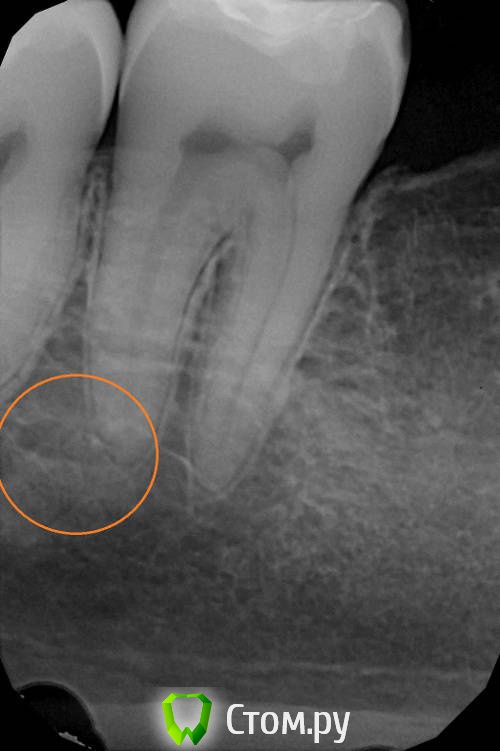

winnt Опубликовано 20 июля, 2014 Автор Поделиться Опубликовано 20 июля, 2014 red_butler, подскажите плиз еще по одному зубу, беспокоит уже больше года, два раза делали эндо, теперь вот иду в пятницу на его удаление (думаю все проблемы из-за выведенного силера) Периодически болит, перкуссия слабоболезненная (особенно со стороны неба) в щеке над ним часто как будто тяжесть или покалывания, утром чувство что есть припухлость в щеке над этим зубом. При пальпации со стороны в сторону зуба - чувство стягивания в щеке усиливается.Спасибо. Ссылка на комментарий

winnt Опубликовано 20 июля, 2014 Автор Поделиться Опубликовано 20 июля, 2014 Забыл добавить, после повторного эндо симптомы пропали на две недели, а потом усилились Ссылка на комментарий

red_butler Опубликовано 20 июля, 2014 Поделиться Опубликовано 20 июля, 2014 Снимки не информативны, выложите срезы Кт в других плоскостях Ссылка на комментарий

winnt Опубликовано 20 июля, 2014 Автор Поделиться Опубликовано 20 июля, 2014 (изменено) Вот еще пару снимков:Видео: видео_1 , видео_2 Изменено 20 июля, 2014 пользователем winnt Ссылка на комментарий